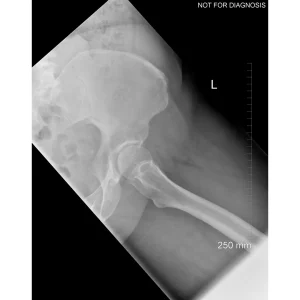

A total hip replacement (also called total hip arthroplasty) is a surgical procedure in which a damaged or worn hip joint is replaced with artificial components. The hip is a ball-and-socket joint, meaning the ball at the top of the thigh bone sits in a socket on the pelvis. During surgery, the damaged ball (femoral head) is replaced with a metal or ceramic ball attached to a stem, and the damaged socket is replaced with a metal cup lined with plastic, ceramic, or metal.